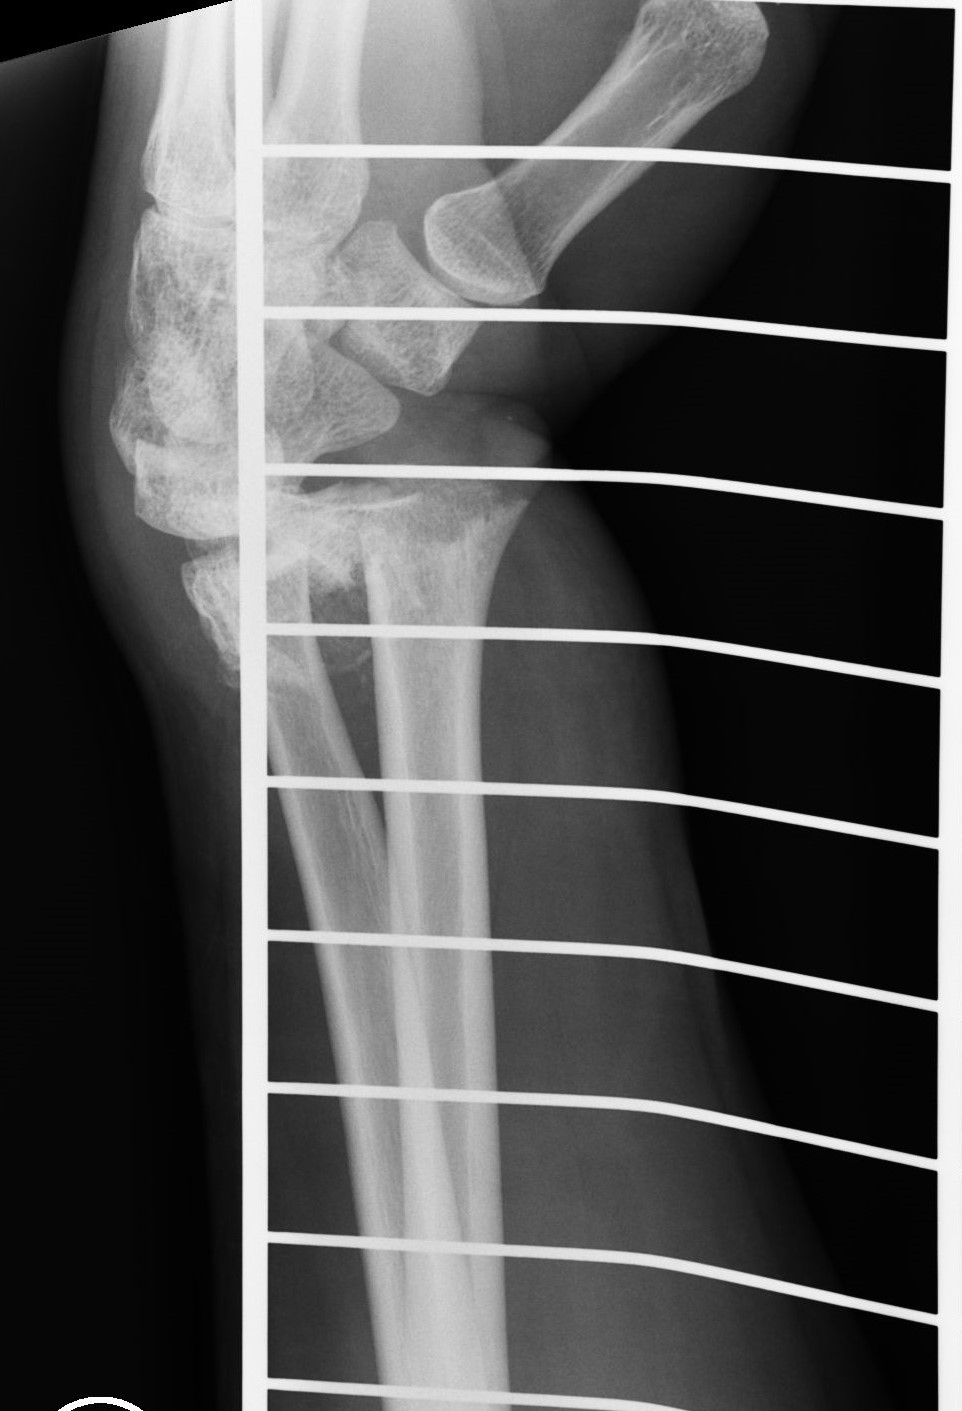

Successful surgery to reduce and fixate with the plate of neglected, displaced fracture of the distal radius

Treatment of neglected, displaced or united distal radial fractures (DRFs) is difficult, because it requires either wedging the almost consolidated fracture and reduction to the correct position, or cutting the united bone and putting it in the correct position (corrective osteotomy). Both treatments are associated with the risk of failure and complications. The paper presents a case of almost fully united DRF in a man, in whom 5 weeks after the injury, and after unsuccessful primary fixation with K-wires, the bone fragments were surgically wedged, aligned and fixed with a palmar plate. The result of treatment after 2 months was satisfactory. Early surgery allowed for a significant shortening of the recovery period and allowed the patient to return to work.